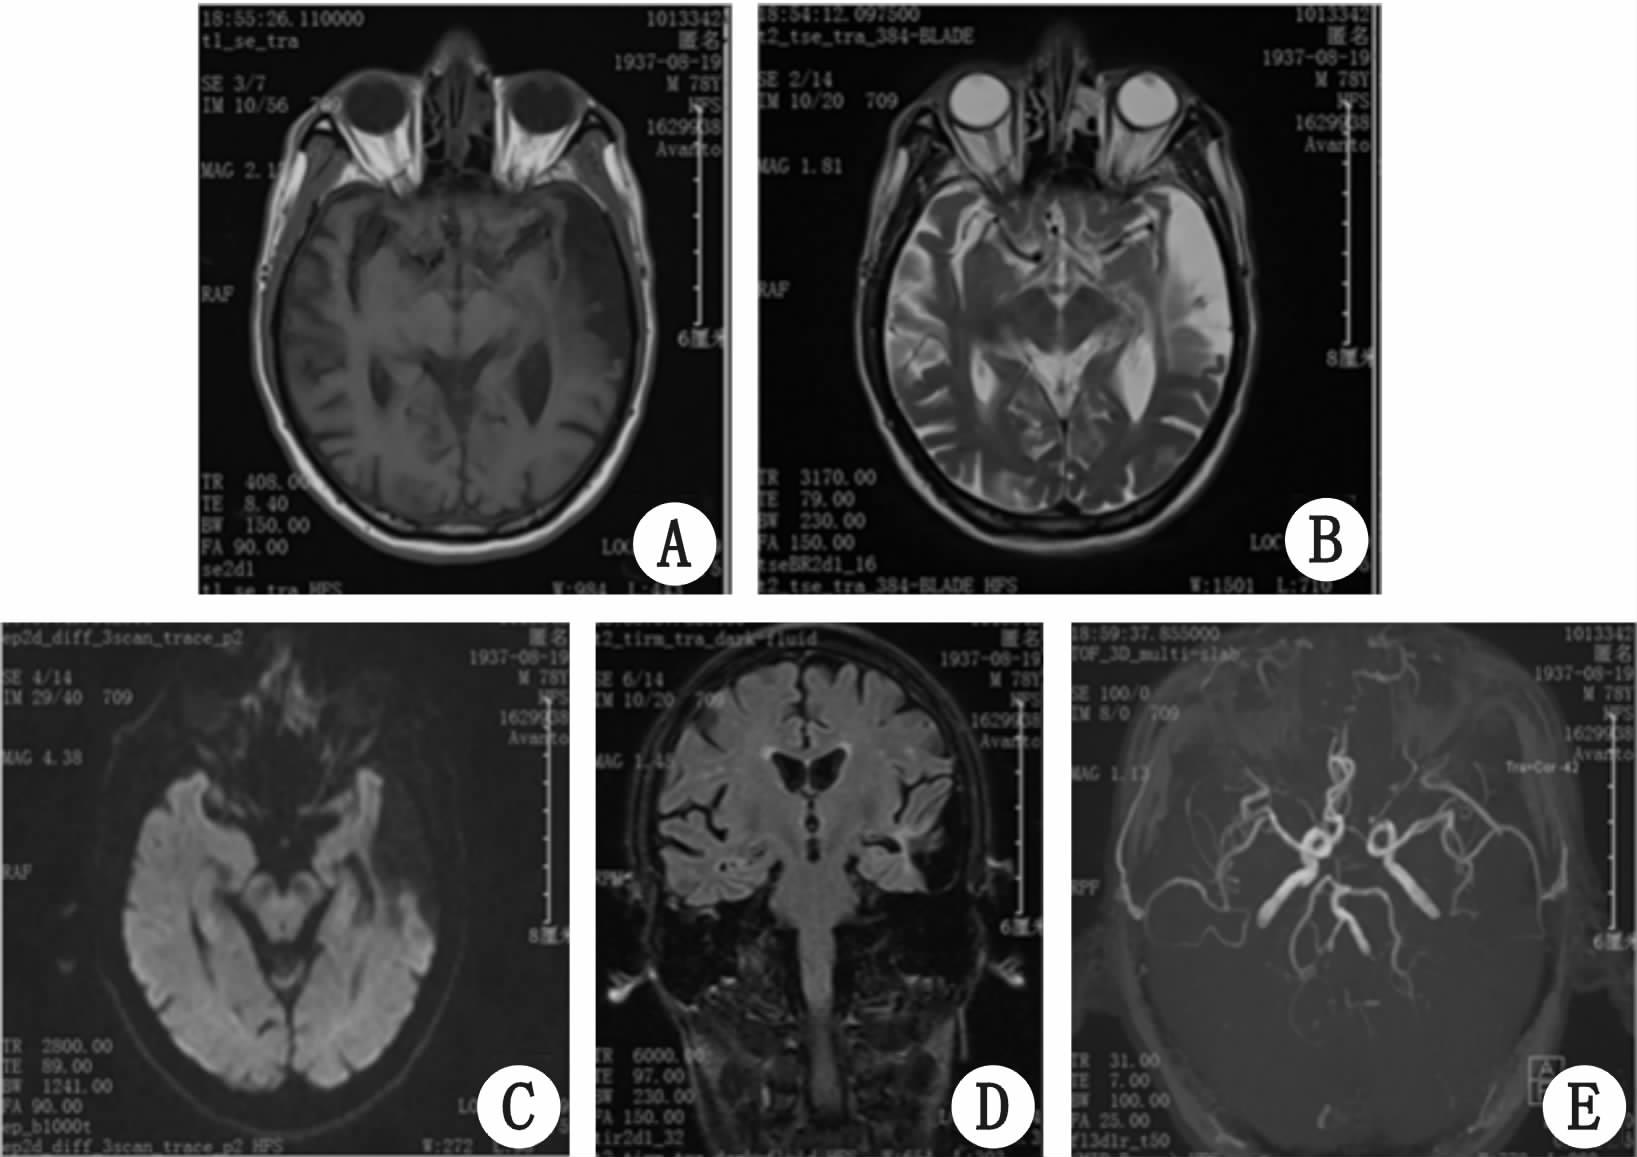

1 资料与方法患者男性,71岁,因“反复头痛2个月余,伴发热1个月”拟“发热待查”于2015年5月6日收住浙江大学医学院附属第二医院感染科。患者2个多月前无明显诱因下出现反复头痛,呈持续性胀痛,无发热,无恶心呕吐,予消炎镇痛药治疗后可缓解。1个月前患者头痛加重,伴反复发热,体温最高达38.5 ℃,无明显畏寒、寒战,无咽痛、流涕、咳嗽、气急、胸闷等其他伴随症状,于当地医院诊断“上呼吸道感染”,给予对症治疗后症状稍缓解,但停药后症状反复发作,性质同前,为进一步诊治入院。入院查体:体温37.8 ℃,神志清,精神可,口角右侧偏斜,颈部稍有抵抗,浅表淋巴结未及明显肿大,心、肺、腹查体无明显异常,四肢肌力及肌张力正常,双侧巴氏征阴性。辅助检查:血白细胞19.5×109/L,中性粒细胞85%,血红蛋白102 g/L,C反应蛋白(CRP)182.9 mg/L,血沉120 mm/第1 h,降钙素原<0.1 ng/mL,大、小便常规正常,肝肾功能正常,抗中性粒细胞胞浆抗体(ANCA)、抗核抗体全套、抗双链DNA抗体均阴性,T-spot检查阴性,血液、尿液细菌培养及特殊病原体检测均阴性。腰穿检查:脑脊液压力16 cmH2O(1 cmH2O=0.098 kPa),潘氏试验(+),葡萄糖5.55 mmol/L,蛋白717 mg/L,氯化物122 mmol/L,有核细胞数348个/μL,中性粒细胞占78%,单个核细胞占22%;涂片:细菌涂片阴性,新型隐球菌阴性,抗酸染色阴性;脑脊液细菌培养阴性。头颅MRI检查:左侧颞叶软化灶,两侧半卵圆区及基底节区少许腔隙灶(图 1)。 患者入院后首先考虑感染性发热,中枢神经系统感染可能,先后予头孢哌酮/舒巴坦、莫西沙星、美罗培南、万古霉素、利奈唑胺等抗生素治疗效果不佳,仍有反复发热,热峰同前,伴头痛,性质同前,多次复查血白细胞、血沉、CRP较前无明显变化。入院2周后复查脑脊液:脑脊液压力15 cmH2O,潘氏试验弱阳性,葡萄糖6.11 mmol/L,蛋白551 mg/L,氯化物125 mmol/L,有核细胞数17个/μL,中性粒细胞占61%,单个核细胞占39%。2015年5月12日患者出现左眼结膜充血肿痛,眼科会诊考虑结膜炎予左氧氟沙星滴眼液滴眼,局部症状无明显好转。2015年5月24日出现右耳廓红肿、疼痛,听力明显下降。追问病史,患者1个多月前曾有双上肢多关节肿痛,鼻梁肿痛,予非甾体消炎镇痛药治疗后好转,未引起重视。经风湿免疫科会诊,考虑复发性多软骨炎合并中枢神经系统损害,予美卓乐片24 mg/d治疗10 d后,血沉及CRP下降至正常,发热、头痛等症状消失,结膜炎及听力好转。出院诊断:复发性多软骨炎,继发性中枢神经系统血管炎。目前患者随访1年余,激素美卓乐6 mg/d维持治疗中,未使用其他免疫抑制剂,病情稳定,无新发头痛、发热、鼻梁及耳廓肿痛等症状,血沉、CRP等炎症指标维持正常。

| A:T1WI 左侧颞叶斑片状长T1信号;B:T2WI 左侧颞叶长T2信号;C:DWI 左侧颞叶病变信号未见增高;D:FLAIR 左侧颞叶病变呈低信号,另双侧大脑皮层下多发斑点状高信号;E:颅脑MRA显示Willis环及其分支血管管壁毛糙,提示动脉硬化 图 1 头颅MRI及MRA检查 |

虽然中枢神经系统受累在RP中较为少见,但多数病例起病急、进展快,现有文献报道的病例中有24例为急性或亚急性起病,若不及时诊断和治疗可能发生不良预后,故需特别重视。另外,RP继发性中枢神经系统受累可发生于其病程的各个阶段,尤其是中枢神经系统症状先于其典型症状发生者,诊断越加困难,容易误诊为其他中枢神经系统疾病,需提高认识,早期诊断和及时治疗是阻止疾病进展和减少永久性神经损害的关键。本例中经追问病史,具有多关节炎及鼻软骨炎特点,为疾病确诊寻找依据所必要。因此对于疑诊RP患者,尤其对于眼、耳、鼻、喉、气管、关节等症状,需全面询问和检查。对于有中枢神经系统症状患者,进一步脑脊液、头颅MRI等检查可提供颅内小血管炎的间接证据,有条件者还可行脑组织活检最终明确诊断。本例脑脊液检查提示非特异炎性改变,蛋白含量增高,糖和氯化物基本正常;头颅MRI检查提示左侧颞叶软化灶,两侧半卵圆区及基底节区少许腔隙灶,其中FLAIR像表现为双侧大脑皮层下多发斑点状高信号,提示皮层下多发性缺血灶,考虑为RP的小血管炎所致;MRA显示的血管主要是主干和大的分支血管,中小血管显示不清,而RP的血管损害主要表现为中小动脉血管炎,表现为小的梗死灶。治疗上多数患者急性期早期应用中到足量糖皮质激素或联合免疫抑制剂治疗可有效控制原发病,改善预后,减少后遗症。